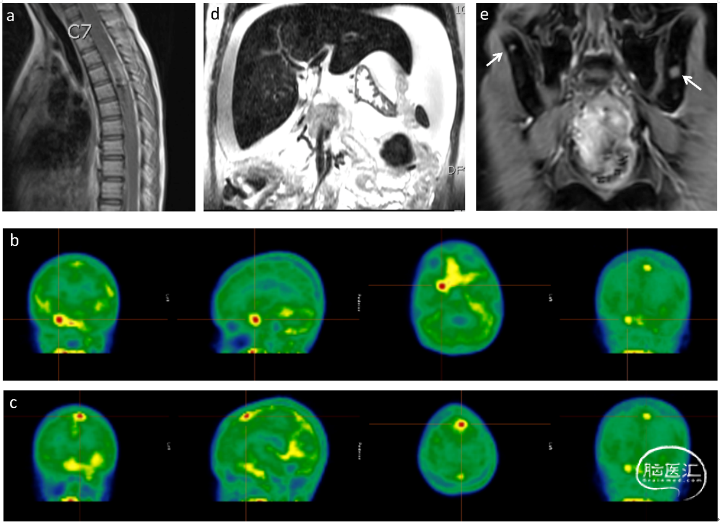

胶质瘤是颅内最常见的恶性肿瘤,目前主要治疗方案是放疗和化疗,但是疗效有限,特别是在高级别胶质瘤中。这也进一步表明探索胶质瘤新的治疗方案的重要性。IDH基因是目前药物研究热点,IDH 抑制剂包括 ivosidenib(AG-120)、vorasidenib(AG -881)、olutasidenib (FT-2102)、BAY1436032等都处于临床试验中。目前正在针对神经胶质瘤患者的临床试验中进行评估。在临床前研究中,DS-1001 已被证明可以抑制突变 IDH1,从而降低 D-2-HG 水平和肿瘤大小。本研究评估IDH抑制剂 DS-1001 药物对复发/进行性 IDH1 突变胶质瘤患者疗效和药效分析。 共入组47名患者(少突胶质细胞瘤 WHO 2级:少突胶质细胞瘤 WHO 3级:星形细胞瘤WHO 2级:星形细胞瘤WHO 3级:星形细胞瘤WHO 4级=4:11:12:11:7),35例患者肿瘤增强,30个(85.7%)接受了强化肿瘤治疗。12例患者肿瘤未增强,8个(66.7%)接受了非强化肿瘤治疗。 47例患者均可进行疗效评估。在35个增强组肿瘤患者中,观察到2个患者出现完全缓解,4名患者出现部分缓解。在12个非增强组肿瘤中:1名患者出现部分缓解,3名患者出现轻微缓解。增强组ORR为17.1%,非增强组ORR达到33.3%。35例增强组肿瘤患者中有15例(42.9%)出现了肿瘤缩小,12例非增强组肿瘤患者中有11例(91.7%)的肿瘤发生肿瘤缩小。其中2例完全缓解的增强型肿瘤患者中。星形细胞瘤患者(IDH突变;WHO 4级)在经历了约174周的完全缓解,目前仍在治疗中。另一位IDH1突变型间变性少突胶质瘤患者在约95周中处于完全缓解,目前仍在治疗中。3例增强组肿瘤患者出现明显的肿瘤缩小,接近完全缓解。在10名治疗响应患者中5人目前继续接受治疗。 在数据截止时,有8名患者(17.0%)仍在接受治疗。增强组胶质瘤患者的治疗中位数持续时间为7.3周,有3名患者(8.6%)继续接受治疗。在非增强组胶质瘤患者中,治疗时间中位数为91.2周,12名患者中有5人(41.7%)仍在接受治疗。增强组胶质瘤组的中位数PFS为10.4周,而非增强组神经胶质瘤组则未达到。 为了评估药物透过血脑屏障以及抑制肿瘤组织中 D-2-HG表达情况,对再次接受手术的疾病进展患者进行了一项探索性研究:评估患者肿瘤组织中DS-1001和D-2-HG的浓度。结果表明在所有切除的肿瘤样本中均检测到高浓度DS-1001药物,表明该药物的脑部渗透效率很高。与第一次手术样本相比,治疗中肿瘤组织中的 D-2-HG 水平极低,表明在DS-1001药物治疗后患者的D-2-HG的含量降低。 DS-1001 药物具有良好的耐受性和良好的脑渗透,复发/进行性 IDH1 突变胶质瘤患者对DS-1001治疗有疗效反应。一项 DS-1001 在未经化疗和放疗的 IDH1 突变 WHO 2 级神经胶质瘤患者中的研究正在进行中 (NCT04458272)。 声明:脑医汇旗下神外资讯、神介资讯、神内资讯、脑医咨询、AiBrain 所发表内容之知识产权为脑医汇及主办方、原作者等相关权利人所有。 投稿邮箱:[email protected] 未经许可,禁止进行转载、摘编、复制、裁切、录制等。经许可授权使用,亦须注明来源。欢迎转发、分享。